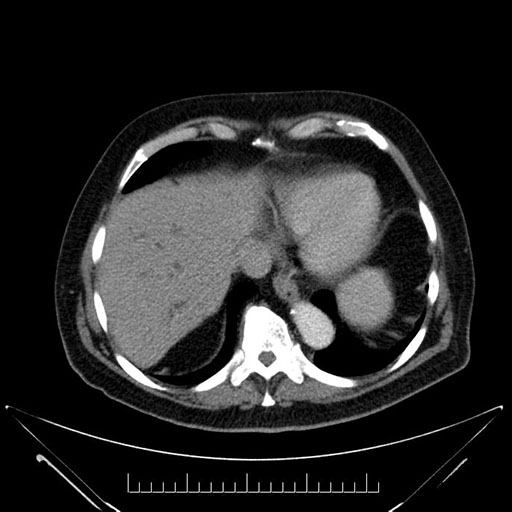

Imaging Analysis

Look through the patient's CT scan to identify any areas of concern for the necessary procedure.

Based on your CT findings, which issue(s) would give reason for "planned slowing down moment(s)" in this case?